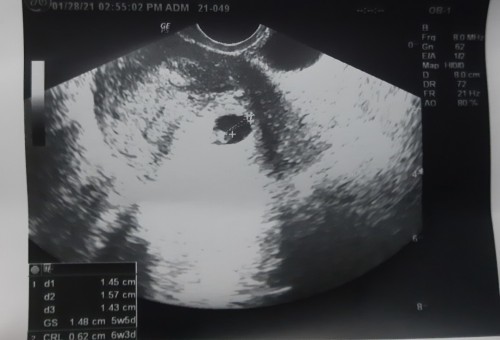

LAST JANUARY 28,2021 IS NAGPA ULTRASOUND PO AKO AND THE RESULT IS 6 WEEKS AND 1 DAY PA BABY KO, SABI NG MAG ULTRASOUND NA DOC.SA AKIN, PERO. NUNG NAG TANONG AMG OB KO WHEN LAST PERIOD KO IS NOV.27,2020 SO SUPPOSEBLY MAG 3 MONTHS NA PO YUNG BABY KO NGAYON. SAAN PO AKO MAG BABASE PO.?? NAGULUHAN NA.PO AKO. #SA NGAYON 8 WEEKS AND 1 DAY NA BABY KO IF.MAG BASE SA ULTRASOUND. #firstbaby #pregnancy #1stimemom